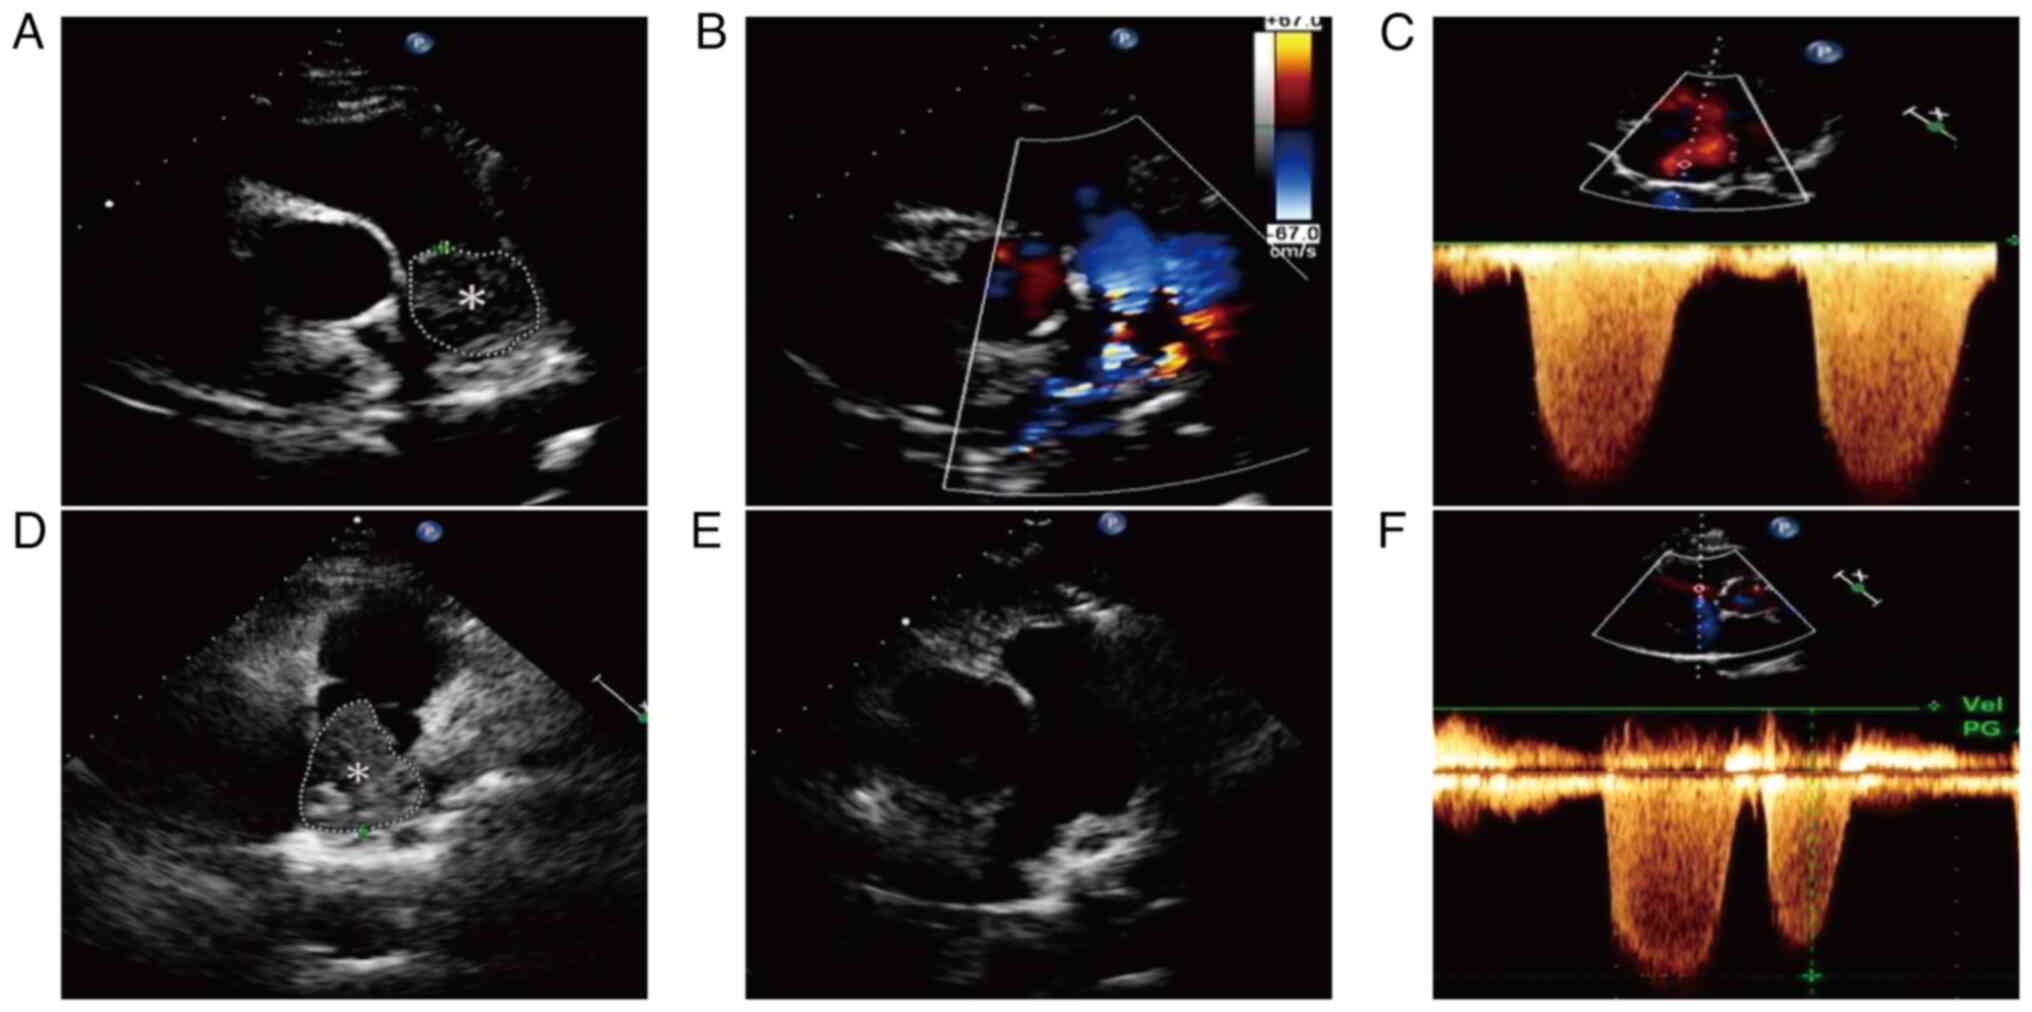

Figure 1.

Transthoracic echocardiography results. (A) A large isoechoic mass (8.79 cm2 in area) was found within the main pulmonary artery before admission, (B) with no blood flow detected in the mass. (C) Severe pulmonary hypertension estimated from tricuspid regurgitation. (D) The size of the isoechoic mass (11.4 cm2) in the main pulmonary artery after anticoagulant therapy had increased compared with its previous state. (E) No abnormal mass echo was detected in the pulmonary artery postoperatively and (F) mild pulmonary hypertension estimated from tricuspid regurgitation. Asterisks indicate the location of the lesion.

Venous ultrasound indicated no signs of thrombosis in the limbs. The electrocardiogram displayed sinus tachycardia, atrial premature contractions and ST-T wave abnormalities. Transthoracic echocardiography (TTE) detected right ventricular enlargement and an isoechoic mass measuring ~8.79 cm2 within the main pulmonary artery (Fig. 1A), which exhibited well-defined margins and a fixed position without evidence of blood filling (Fig. 1B). Additionally, TTE imaging demonstrated severe pulmonary hypertension (mean pulmonary artery pressure, 94 mmHg; normal range, 18–25 mmHg) and marked tricuspid regurgitation (Fig. 1C). Computed tomography pulmonary angiography (CTPA) was performed to further investigate the suspicion of a PTE. The imaging revealed regions of decreased density in the main pulmonary artery, the proximal segment of the right pulmonary artery, the left pulmonary artery, the left upper lung and branches of the left lower pulmonary artery (Fig. 2A), with no nodules in the lungs (Fig. 2B). Furthermore, localized enlargement measuring a diameter of ~37 mm was noted in the main pulmonary artery. Minimal fluid accumulation was also identified in both the pericardium and right pleural cavity. The initial diagnosis was PTE, for which the patient received subcutaneous injections of low molecular weight heparin (4,000 IU every 12 h) and oral warfarin (2.5 mg per day) anticoagulation therapy. However, despite a week of treatment, the patient's clinical symptoms gradually worsened. Subsequent repeat TTE was performed to assess the efficacy of anticoagulant therapy, revealing an increase in the size of the isoechoic mass within the main pulmonary artery (~11.4 cm2) (Fig. 1D). The patient was promptly transferred to the Department of Cardiothoracic Surgery for further intervention. Under general anesthesia and cardiopulmonary bypass, pulmonary endarterectomy was conducted at 9 days post-admission to alleviate the deteriorating clinical symptoms, revealing a 15×5-cm mass in the main pulmonary artery (Fig. 3), closely adherent to its intima and extending throughout both the left and right pulmonary arteries. The mass was successfully excised, with intraoperative transesophageal echocardiography confirming the absence of residual masses in the main pulmonary artery and no marked tricuspid valve regurgitation. The resected specimens were fixed in 10% formalin at room temperature for 24 h for histopathological examination. Histopathological staining and immunohistochemistry were performed using 4-µm thick paraffin-embedded sections, and the specific protocol was carried out in accordance with the method described by Neuville et al (5). The BOND-MAX fully automatic IHC and ISH staining system (Leica Microsystems) was used for immunohistochemical staining. Slides were inspected under a light microscope (Olympus BX51TF; Olympus Corporation). Hematoxylin and eosin staining revealed that the tumor cells exhibited an epithelioid and short fusiform morphology, with marked heterogeneity in cell density. Tumor cells were preferentially aggregated around blood vessels, accompanied by desmoplastic mucinous degeneration and localized hemorrhage. Notably, the tumor cells displayed pronounced atypia, with identification of pathological mitotic figures (Fig. 4A). Immunohistochemical examination revealed positive vimentin (cat. no. RTU-VIM-V9-QH; AQ Medical Technology) and Ki-67 (40%) (antibody dilution, 1:150; cat. no. NCL-L-Ki67-MIB1; AQ Medical Technology) staining, but negative staining for anaplastic lymphoma kinase (ALK; cat. no. GT226602; Gene Tech, Co., Ltd.), CD34 (cat. no. RTU-END-QH; AQ Medical Technology), CD117 (cat. no. RTU-CD117-QH; AQ Medical Technology), CD163 (cat. no. RTU-CD163-QH; AQ Medical Technology), cytokeratin (CK; antibody dilution, 1:200; cat. no. NCL-L-AE1/AE3-601; AQ Medical Technology), erythroblastosis transformation specific-1 related gene (ERG-1; cat. no. RTU-ERG-QH; AQ Medical Technology), p53 (antibody dilution, 1:100; cat. no. NCL-L-P53-DO7; AQ Medical Technology), S100 (cat. no. RTU-S100-QH; AQ Medical Technology) and smooth muscle actin (SMA; cat. no. RTU-SMA-QH; AQ Medical Technology) (Fig. 4B-L). The final diagnosis of PAIS was confirmed based on the results of the pathological examination and the specific tumor localization (6,7).

Following surgery, the patient experienced a satisfactory recovery with notable improvement in clinical symptoms. A postoperative TTE revealed no abnormal mass in the pulmonary artery and a marked decrease in pulmonary artery pressure (34 mmHg) compared with preoperative levels (Fig. 1E and F). Despite the recommendation for a positron emission tomography-CT (PET-CT) scan, the patient declined and was discharged in May 2020. Subsequently, the patient opted to undergo treatment with oral anlotinib (12 mg on days 1–14) according to the 2019 Chinese Society of Clinical Oncology treatment guidelines for soft-tissue sarcoma (8) and due to the demonstrated significant efficacy of anlotinib in treating soft-tissue sarcoma in multiple clinical trials (9). In December 2020, the patient reported chest tightness, dyspnea and chest/back pain. An enhanced CT scan of the chest performed on 3 days later revealed a low-density filling defect in the main pulmonary artery along with a 10-mm nodule in the left upper lobe initially suspected to be metastatic lesions (Fig. 2C and D). The patient opted to continue oral anlotinib treatment while remaining hesitant to modify the treatment regimen. A subsequent enhanced CT scan of chest and abdomen performed in March 2021 showed substantial enlargement of the low-density lesions within the main pulmonary artery (~68×67 mm), as well as multiple fresh soft-tissue masses in the left lung; however, no abnormalities were observed within the abdominal region (Fig. 2E and F). Concurrently, the levels of tumor marker CA125 were increased to 66.9 U/ml (reference value, 0–35 U/ml) and exhibited a progressive upward trend as the disease progressed. By April 2021, the level of this marker had peaked at 267 U/ml.